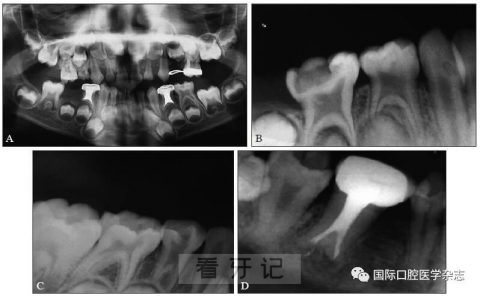

A:患儿74、84为牛牙症;

B:患儿哥哥84、85为牛牙症;

C:患儿姐姐84为牛牙症;

D:患儿母亲46为牛牙症。